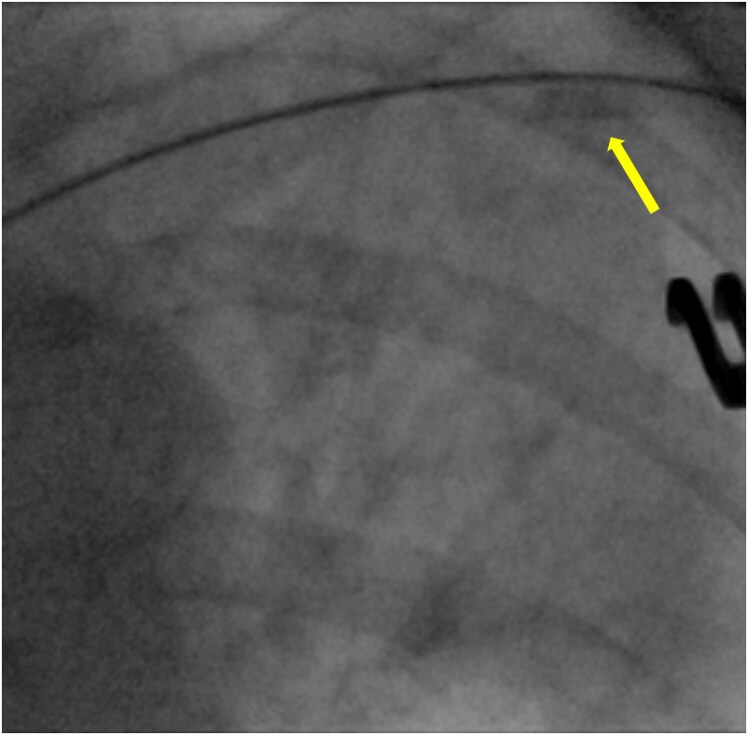

Case summary: An 82-year-old lady underwent PPM implantation for symptomatic 9-second sinus pause. During procedure, the anchoring sleeve from the atrial lead embolized through cephalic vein to the left superior lingular artery. The patient remained haemodynamically stable and multimodality imaging demonstrated only a small affected area of lung with patent pulmonary blood flow distal to the sleeve. Therefore, the patient was managed with anticoagulation alone and has remained well at 26-month follow-up.